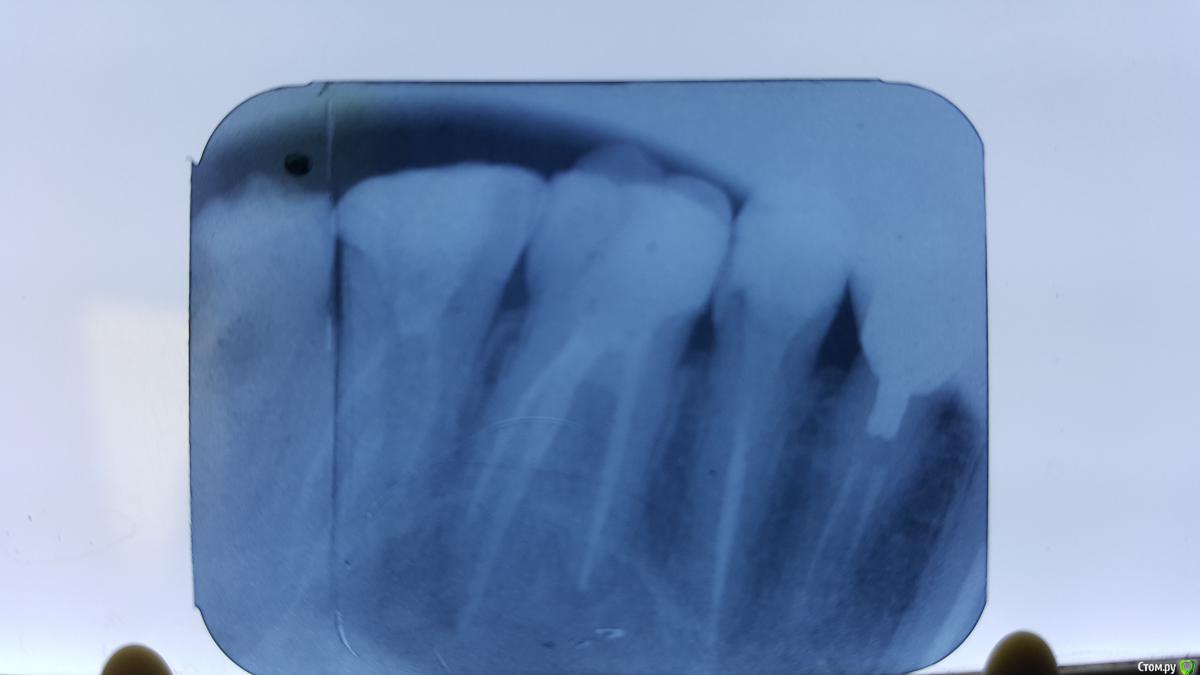

Rasl05 Опубликовано 5 апреля, 2016 Поделиться Опубликовано 5 апреля, 2016 Доброго времени суток уважаемые доктора. Нужна ваша помощь. Вчера вечером пришел пациент лет 22 с жалобами на боль при накусывании 16 зуба. Перкуссия зуба и пальпация по переходной складке болезненна. На снимке как мне кажется образовалась киста. Можно ли сохранить этот зуб если да то как? Если удалять то каков план лечения после удаления. За ранее благодарю за ответы. Ссылка на комментарий

red_butler Опубликовано 5 апреля, 2016 Поделиться Опубликовано 5 апреля, 2016 На снимке как мне кажется образовалась киста. по данному снимку какие либо вводы делать нельзя. Сделайте Кт Можно ли сохранить этот зуб если да то как? повторное эндоВы стоматолог? Почему вообще возникают такие вопросы? Ссылка на комментарий